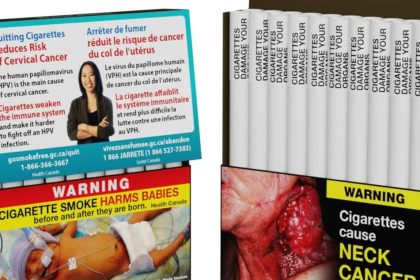

Kanada, her bir sigaranın üzerine “sağlığa zararlı” uyarısı koyacak

Kanada, 2001'de sigara paketlerine "sağlığa zararlı" uyarısı koyarak dünyada öncü olmasının ardından,…